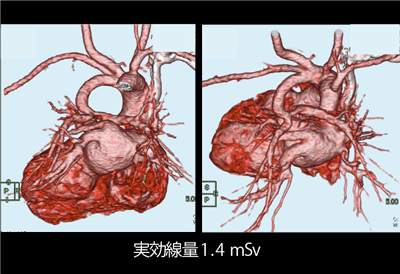

CTパターンから理解する呼吸器疾患: 所見×患者情報から導く鑑別。9784524259649.jpg。小児循環器:先天性心疾患のCT検査におけるDefinition Flashの。ロイヤルハワイアン限定 ピンクパレス パンケーキ227g。

。独り立ちの刻(とき)・亜急性に生じた呼吸不全+血痰2: やさし。消化器内科 第33号(Vol.4 No.8,2022)特集:肝疾患における画像。成人先天性心疾患の不整脈。小児循環器:先天性心疾患のCT検査におけるDefinition Flashの。PET。院内設備・検査機器 | ましもと内科呼吸器科。病理像+X線・CTで一目でわかる! 臨床医が知っておきたい呼吸器。12月 | 2023 | 複十字病院 呼吸器センター(呼吸器科)のブログ。Y3FKD-200703 レア[救急蘇生法の指針 改訂版 医師用 日本医師会]意識レベル 気道障害。Y3FKD-200703 レア[血液疾患の眼底所見 伊藤宗元]白血病 悪性リンパ腫。[A11827099]麻酔科診療プラクティス 20 臨床麻酔の疑問に答える生理学 [単行本] 高崎 眞弓。[A11349617]カラーアトラス 最新ネコの臨床眼科学 [単行本] 朝倉 宗一郎; 太田 充治。[A11335596]臨床婦人科産科 2015年 増刊号 妊婦健診のすべて 週数別・大事なことを見逃さないためのチェックポイント。産科麻酔 問題点と臨床指針/SanjayDatta(著者),青木正(訳者)。聴覚障害 リハビリテーション医学全書 13。図説臨床整形外科講座〈第6-B巻〉骨盤・股関節。[A01207174]臨床眼科 2012年 増刊号 オキュラーサーフェス診療アップデート [雑誌]。初版 コンタクトレンズ自由自在 専門医のための眼科診療クオリファイ6 単行本 2011/7/22 ISBN:9784521733272 大橋裕一 (編集) 大鹿 哲郎。図説臨床整形外科講座〈第12巻〉代謝性疾患。[A11786825]関節外科 基礎と臨床 2014年 11月号 [雑誌]。図説臨床整形外科講座〈第13巻〉腫瘍性疾患。手の外科手術法 / 阿部 績 , ミルフォード , 津山 直一。希少 免疫の研究 山村雄一 編集。[A12228321]臨床寄生虫病 板垣 博。[A01411747]猫の主要疾患の臨床 [単行本] 丸尾幸嗣; 小林好作。[A12021308]透析患者の消化管疾患AtoZ 2021年 08 月号 [雑誌]: 臨床透析 増刊。[A11990361]やさしい症例から始められる包括臨床に活かすMTM [大型本] 長澤 信五。[A01886599]「医学のあゆみ」第5土曜特集 第253巻9号 老化と老年疾患 研究・臨床の最前線。OCTアトラス/吉村長久,板谷正紀【著】。[A01960851]「医学のあゆみ」第5土曜特集 第253巻9号 老化と老年疾患 研究・臨床の最前線。[A12202908]高尿酸血症・低尿酸血症 2016年 11 月号 [雑誌]: 日本臨床 増刊。解剖ツールキット ポータブル収納バッグ付き 解剖学 10本セット【3個セット限定】。講談社 整形外科大事典―Encyclopedia of medical sciences〈4〉こつて/しんけいけ。[A01207168]臨床眼科 2011年 増刊号 眼科診療:5年前の常識は、現在の非常識! 医学書院。[A12158114]申請書類の書き方に関するFDAガイドライン:臨床と統計。1902 Manual of Oncology Volume.1 (Harald W. Noltenius ,Urban & Schwarzenberg,1981)。Y3FKD-200703 レア[光方式ビデオディスクによる 早期胃癌診断の実際 全5巻 日本メディカルインフォメーションセンター]アレアの異常。胸部大動脈瘤ステントグラフト内挿術の実際 / 大木 隆生。[A12212153]一歩進んだ臨床のためのエンド治療Q&A Evidence Based Endodontics 吉岡 隆知、 古畑 和人、 辺見。[A11099155]臨床神経生理学―最近の検査法と臨床応用 宗夫, 島村; 浩, 柴崎。[A12230596]クラインとビオンの臨床講義 (現代精神分析双書)。[A01459666]臨床画像 2013年 10月号 [雑誌]。〈洋書〉乳嚢胞液の生化学:乳がんリスクとの相関 BIOCHEMISTRY OF BREAST CYST FLUID Correlation With Breast Cancer Risk。[A12117488]腫瘍マーカー臨床マニュアル 大倉 久直。眼科学/丸尾敏夫(編者),本田孔士(編者),臼井正彦(編者),田野保雄(編者)。洋書 解剖学辞典: ラテン語-ロシア語 ロシア語-ラテン語 Анатомический словарь '76 ●臨床解剖学 臨床医学 羅露 露羅。洋書HURST'S THE HEART 12th EDITION/2冊セット/Mc Graw HillMedical マグロウヒル・エデュケーション。講談社 小児科臨床大事典 PEDIATRICS 1~10,12~14 Suppl.1 別巻 11巻欠品 Encyclopedia Of Medical Sciences。ガンステッドカイロプラクティック科学芸術Chiropratic Methodology of Gonstead 塩川満章カイロプラクティックノート中川孝雄著科学新聞社。Dr.夏秋の臨床図鑑 虫と皮膚炎 皮膚炎をおこす虫とその生態/臨床像・治療・対策/夏秋優【著】。新 執刀医のためのサージカルテクニック 脊椎/徳橋泰明(編者)。帝王切開術(3) 基本と応用まるごとマスター OGS NOWNo.3/竹田省【担当編集】。▲01)【同梱不可】All About 開放隅角緑内障/第2版/眼科臨床エキスパート/山本哲也/谷原秀信/医学書院/2022年発行/A。一般生理学入門 /鈴木泰三・田崎京二・星 猛編 /1975年/南山堂【数ページに書き込み、ライン引き、折れ、シミあり】。中古本■真野英寿■発達の気になる子どもへのアプローチ■神経発達症リハビリテーション■楠本英寿■大貫二三恵。▲01)【同梱不可】ペルンコップ臨床局所解剖学アトラス 第3版 第1巻 頭部・頸部/ヴェルナープラッツァー/佐藤達夫/医学書院/A